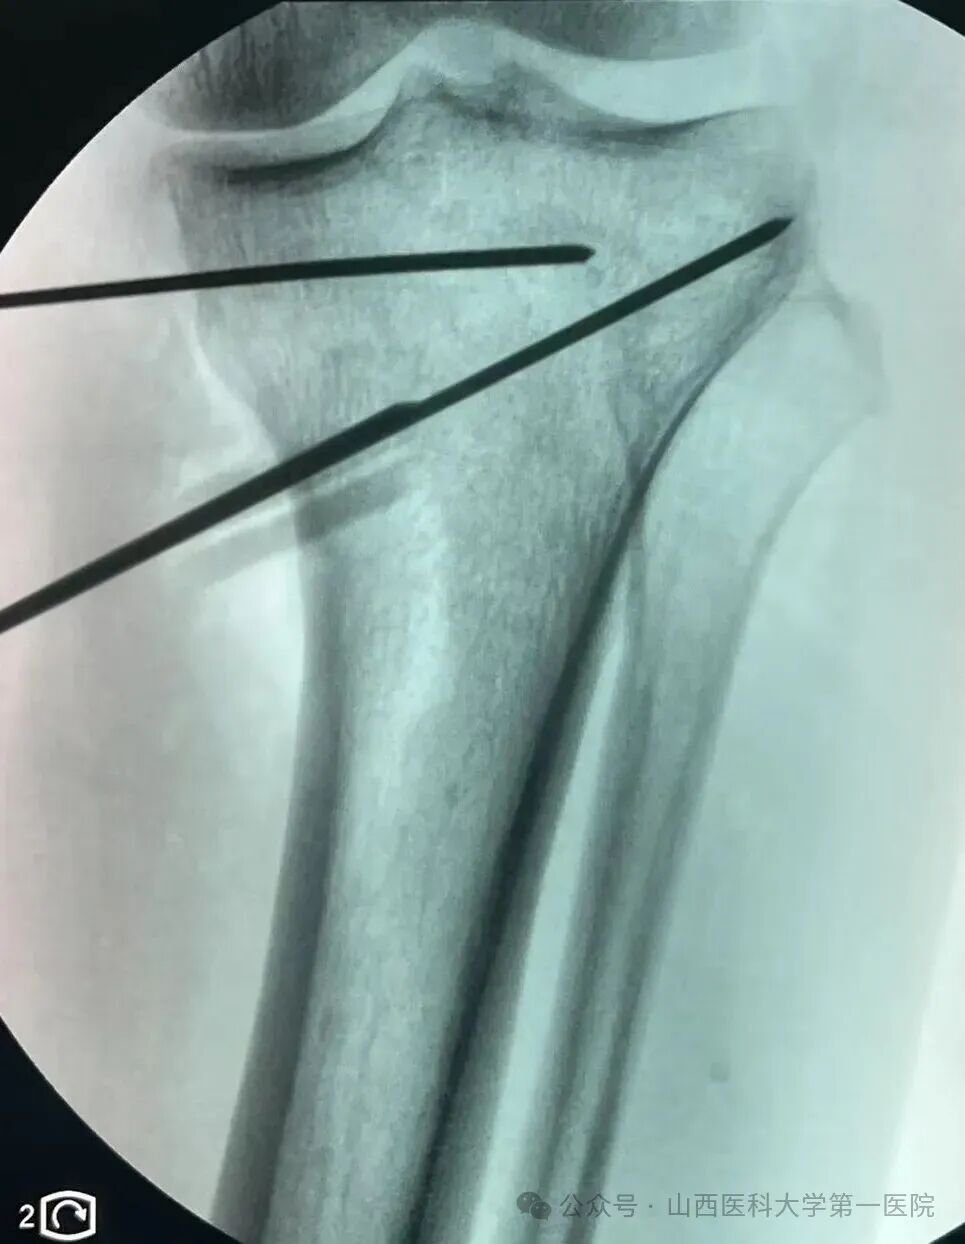

术中杨自权主任在关节镜下为患者修复损伤半月板

术中通过3D-PSI导板进行截骨